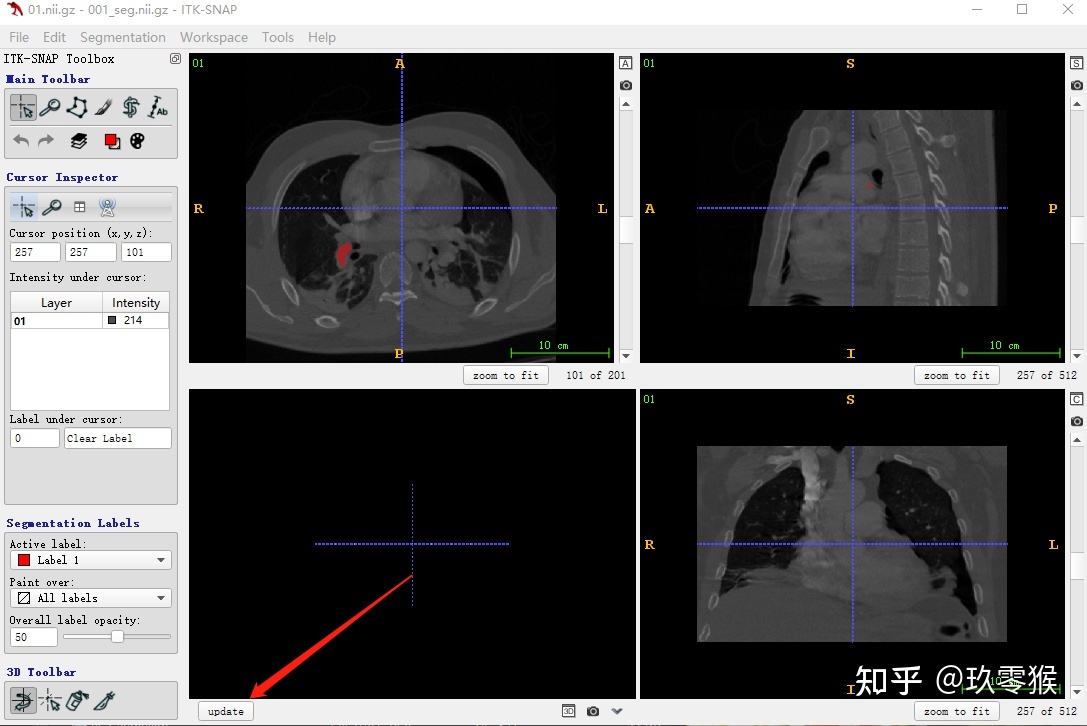

1、导入医学图像( nii.gz文件)

File->Open Main Image

点击 Browse... (切记不能有中文路径) -> Next

2、载入相应的分割图数据( nii.gz文件)

Segmentation - > Open Segmentation -> Browse... -> Next

3、3D可视化

左键可以选装3D图像

右键加滚轮可以缩放3D图像